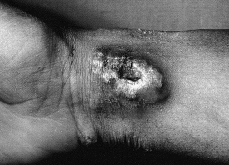

En la exploración física se observó en cara anterior de muñeca derecha una placa de consistencia pétrea con límites irregulares a la palpación, infiltrada, eritematoviólacea, con zonas costrosas y centro levemente ulcerado (Fig. 1).

FIG. 1.--Placa en muñeca de consistencia pétrea y centro ulcerado.